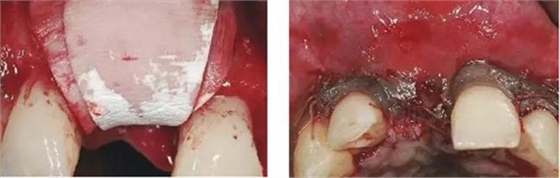

圖8、從上腭獲取結(jié)締組織縫合在黏骨膜瓣上,進行軟組織增量。為了使得黏骨膜瓣充分減張情況下關(guān)閉,應(yīng)該使用瓣的分層技術(shù)。使用6-0或者5-0的可吸收線縫合關(guān)閉傷口。4個月后進行二期手術(shù)時通過分裂瓣技術(shù)將色素沉著的牙齦向冠方復(fù)位以恢復(fù)其原來的自然外形(在此沒有展示)。